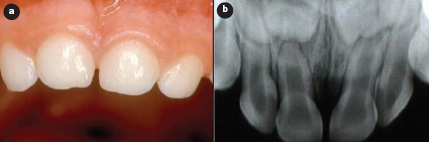

Une semaine plus tard, la muqueuse était presque guérie et la dent présentait une légère mobilité. Aucune altération n'était apparente à la radiographie. Douze mois après le traumatisme, l'examen clinique n'a révélé aucune décoloration de la couronne dentaire, ni aucune douleur, et les caractéristiques de la muqueuse étaient normales (ill. 2a). L'examen radiographique n'a montré aucune altération (ill. 2b).

Ill. 2 : Vues clinique et radiographique, un an après le traumatisme : a) l'examen clinique montre une muqueuse normale et l'absence de décoloration de la couronne dentaire; b) l'examen radiographique présente des caractéristiques normales.

Au moment de l'examen clinique effectué 6 ans après le traumatisme, l'incisive centrale supérieure droite permanente avait fait éruption dans la cavité buccale (dent 11) et présentait des signes de malformation, de décoloration et de dilacération de la couronne (ill. 4a et 4b). Ces défauts ont été restaurés avec une résine composite photopolymérisable.

Ill. 4 : Malformation coronaire des dents permanentes : a) vue intrabuccale montrant une hypoplasie de l'émail sur l'incisive centrale supérieure droite permanente et une hypoplasie circulaire de l'émail sur l'incisive centrale gauche permanente; b) vue intrabuccale montrant la dilacération de la couronne de la dent 11 et la décoloration.